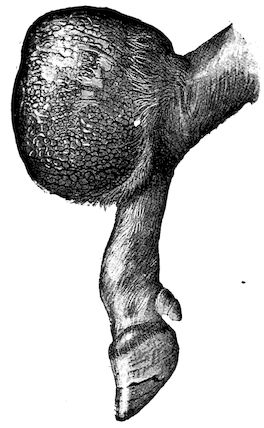

Fig. 4.—Deformity of the face in the horse shown in Fig. 2.

The flat bones are particularly liable to this change, which is common to domesticated animals. The bones of the head are the first to suffer; later those of the pelvis. The lower jaw becomes swollen, particularly about the centre of the branches which may attain three, four, or five times, their normal thickness.

The depression in the submaxillary space disappears. The upper jaw undergoes similar changes, becoming deformed and thickened until the cavities of the sinuses and the hollow appearance of the palate are lost, while the face is so changed that it cannot be recognised as that of a horse, goat, etc.

The molar teeth are almost buried, their tables alone being visible at the bottom of a depression, the edges of which rise above the neighbouring parts (pig).

Mastication is clearly impossible, the jaws appear paralysed, the muscles powerless, and only swallowing is possible, a fact which explains why life is only prolonged to this stage in animals which can be fed with a spoon or bottle (pigs and goats). The bones of the cranium, although greatly changed in texture, are always less deformed than those of the face.

The changes are such that it is often easy with a mere post-mortem knife to cut the head completely in two. Osseous tissue, properly so-called, has disappeared.

All the constituent tissues, with the exception of the skin and muscles, i.e., the bone, periosteum and aponeuroses, have the appearance and consistence on section of the fibro-lardaceous tissue seen in chronic inflammation.